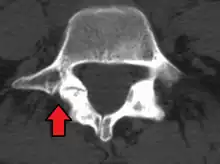

MRI of L5-S1 anterolisthesis

Anterolisthesis L5/S1

Anterolisthesis L5/S1. Blue arrow normal pars interarticularis. Red arrow is a break in pars interarticularis